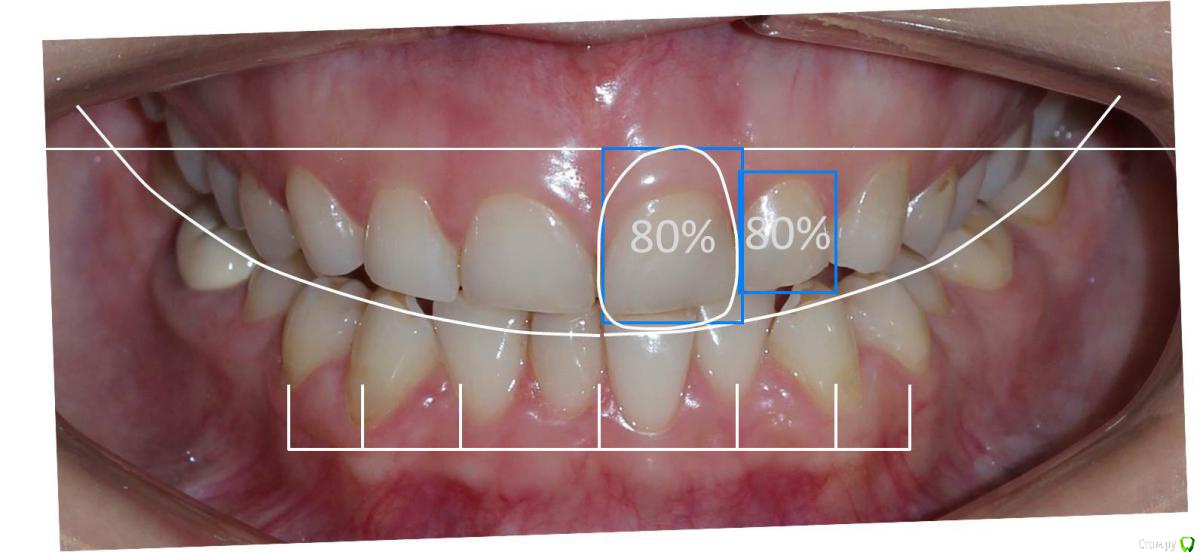

Сева северный Опубликовано 9 декабря, 2015 Поделиться Опубликовано 9 декабря, 2015 Ко мне обратилась молодая девушка, не довольная своей улыбкой. Был проведен этап планирования.... анализ улыбки ..(DSD), (wax up) и примерка (mock up)Проведенный этап...с мотивировал пациентку . 15 Ссылка на комментарий

Сева северный Опубликовано 10 декабря, 2015 Автор Поделиться Опубликовано 10 декабря, 2015 Отлично! C мокапом улыбка перестала быть десневой, пластмасса лежит на десне? как на картинке с цифровым планированием? Или просто пациентка улыбнулась не так открыто?Да... на десне. В этом и был смысл планирования, посмотреть как будет выглядеть зубы. при удлинении в корневую сторону. Ссылка на комментарий

Сева северный Опубликовано 11 декабря, 2015 Автор Поделиться Опубликовано 11 декабря, 2015 (изменено) Как вы определяете когда надо делать хир.удлинение коронки, а когда просто удлинить без хирургии. По стертым режущим краям,похоже что не было нарушения прорезывания...зондировали до ЦЭС? Или по десневой улыбке скромной решили пойти апикально?Я сделал только планирование.... Ход мысли был следующий: Длина центральных резцов 19-20 мм. Длина коронковой части зуба центрального резца 7-8 мм. Оптимальная длина 10.5. По результату пациентка с мотивирована на ортодонтию , с коррекцией gammy smile. Решение по хирургии, примем по результатам ортодонтии. Изменено 11 декабря, 2015 пользователем Сева северный 1 Ссылка на комментарий